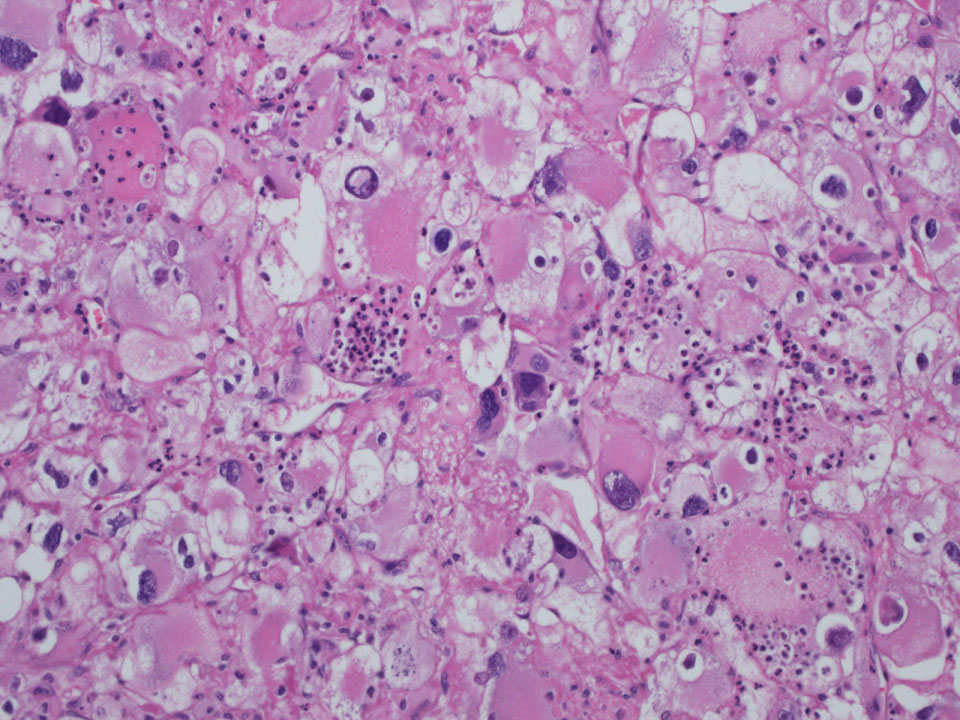

Consensus grade: WHO/ISUP grade 4

Rhabdoid area in a clear cell RCC |

Rhabdoid cells |